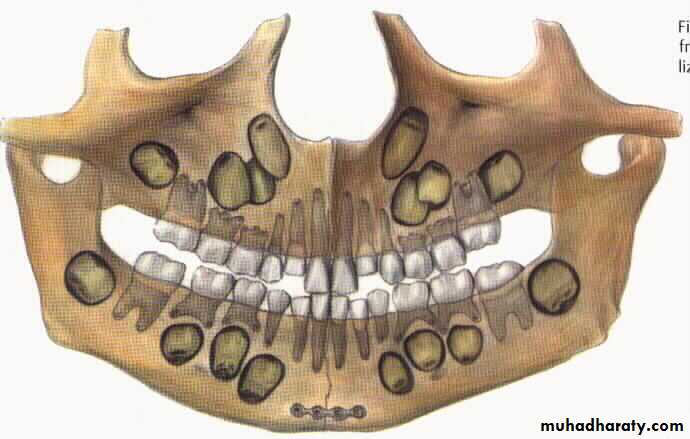

Fracture mandible in children

Close reduction

Open reduction and fixation

Plating at the inferior border

Resorpable plates

It is indicated in the young children and for edentulous patient.In children below 12 years age cap splints are made and circumferential wiring done so that injury to the tooth buds can be avoided.

Similarly in edentulous patient , who also have a compromised blood supply, and no teeth to give inter maxillary fixation, this technique is very helpful.